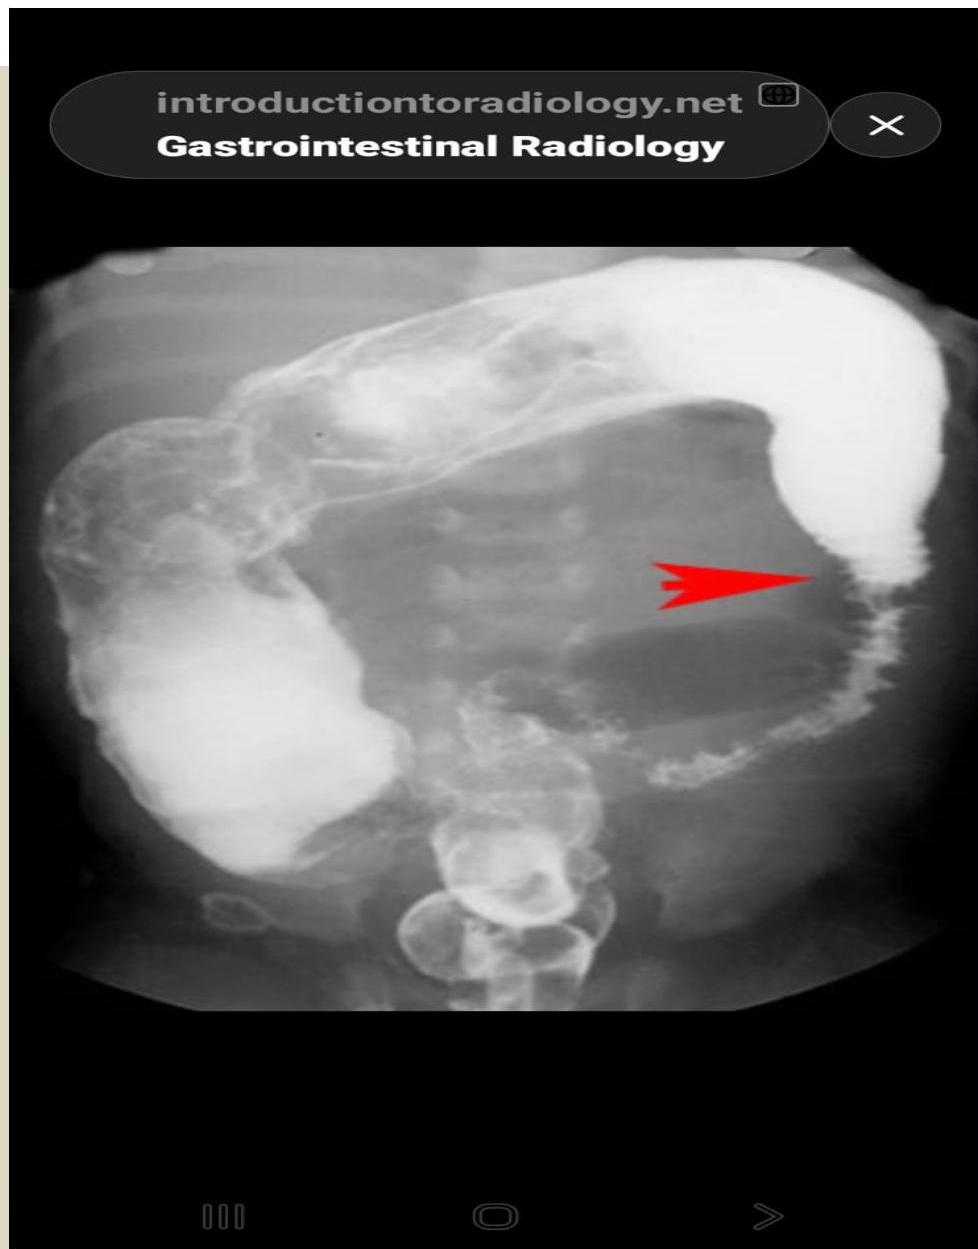

- Barium enema: Shows a transitional zone where a market change in caliber occurs, with the dilated normal colon above and the narrowed aganglionic below (should not be done in patient suspected of having enterocolitis → perforation).

- Proximal Dilated Bowel (Normoganglionic)

- Transition Zone (hypoganglionic)

- Contracted Distal Bowel (aganglionic)

The transition zone is in the mid-descending colon.